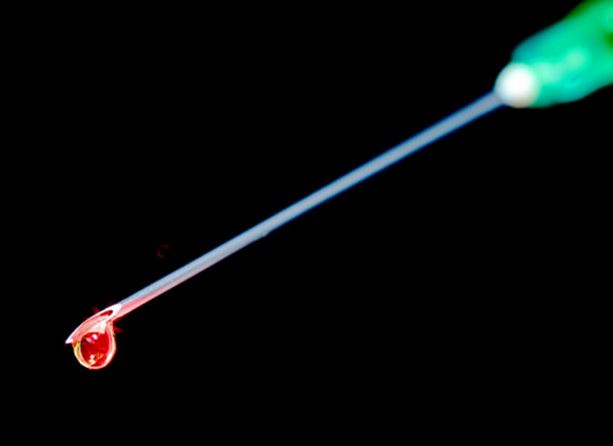

Ministerul Afacerilor Externe informează cetăţenii români asupra faptului că Organizaţia Mondială a Sănătăţii (OMS) a declarat că problema răspândirii internaționale a polio-virusurilor (virusurilor poliomielitei) constituie un risc şi o Urgenţă de Sănătate Publică de Importanţă Internațională (USPII).

În acest sens, OMS a emis o recomandare de vaccinare (cel puţin pentru următoarele 12 luni) cu o doză de vaccin polio inactiv (VPI) a tuturor persoanelor care călătoresc pe termen scurt sau lung în Afganistan, Camerun, Guineea Ecuatorială, Etiopia, Irak, Israel, Madagascar, Mali, Nigeria, Pakistan, Somalia, Siria şi Ucraina. Se recomandă cetățenilor români să se informeze asupra atenționărilor emise de către instituţiile medicale autorizate din statele sus-menţionate referitor la această problematică.Vaccinarea se va face cu patru săptămâni înaintea călătoriei sau pentru cazuri de urgență chiar înaintea plecării. Vaccinarea va fi consemnată pe un format tip al OMS „Certificat de vaccinare sau profilaxie” (carnetul galben), specificat în Anexa nr. 6 a Regulamentului Sanitar Internaţional 2005, care poate fi accesat la adresa dedicată de Internet http://www.who.int/ihr/ports_airports/icvp/en, iar acest carnet va însoţi documentele de călătorie.